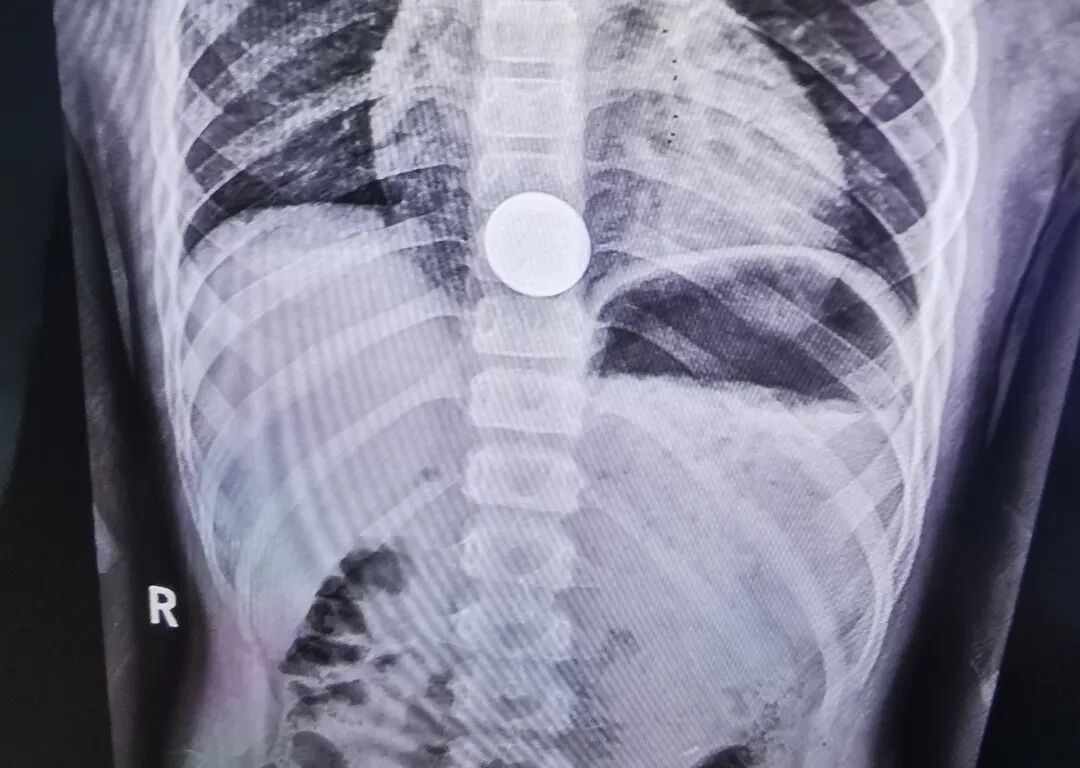

5月29日下午5点半,一对家长抱着孩子急匆匆奔入新泰市中医医院综合楼三楼小儿外科门诊,小儿外科坐诊专家询问得知患者来自新泰羊流,该五岁孩子在玩硬币时,不小心把一枚1元硬币从嘴里吞下,在当地卫生院拍胸片后建议到上级医院诊疗。

当妈妈抱着小患者出现在李迎吉主任的面前时,孩子用手捂着自己的胸口下方,一直喊着:“妈妈,疼!妈妈,疼!……”看过孩子妈妈手机里拍存的胸部片子,发现硬币卡在食管下段、膈肌上水平李迎吉介绍,因为孩子年龄小,贲门狭窄,硬币卡在食管下端下不去,在此部位较危急,食管痉挛导致孩子异常疼痛,时间长了还会引起出血、溃疡甚至穿孔。

开始实施胃镜取硬币前,李迎吉让孩子含住胃镜口垫,让孩子的父母固定好小患者的头部和上身部,同时护士长陈娜用温柔而又温暖的言语对小朋友进行了成功的安抚,孩子的情绪逐渐平静下来,李迎吉及时抓住机会,将胃镜软管轻轻地从小患者的口腔往里探进,循腔进镜在食管下端,发现硬币,李迎吉迅速用异物取出钳夹住硬币,快速而轻柔地往外拉,一元硬币应声而出。大家终于松了一口气,孩子的父亲高高地竖起大拇指,眼里满是感激。

(“惹事”的硬币)